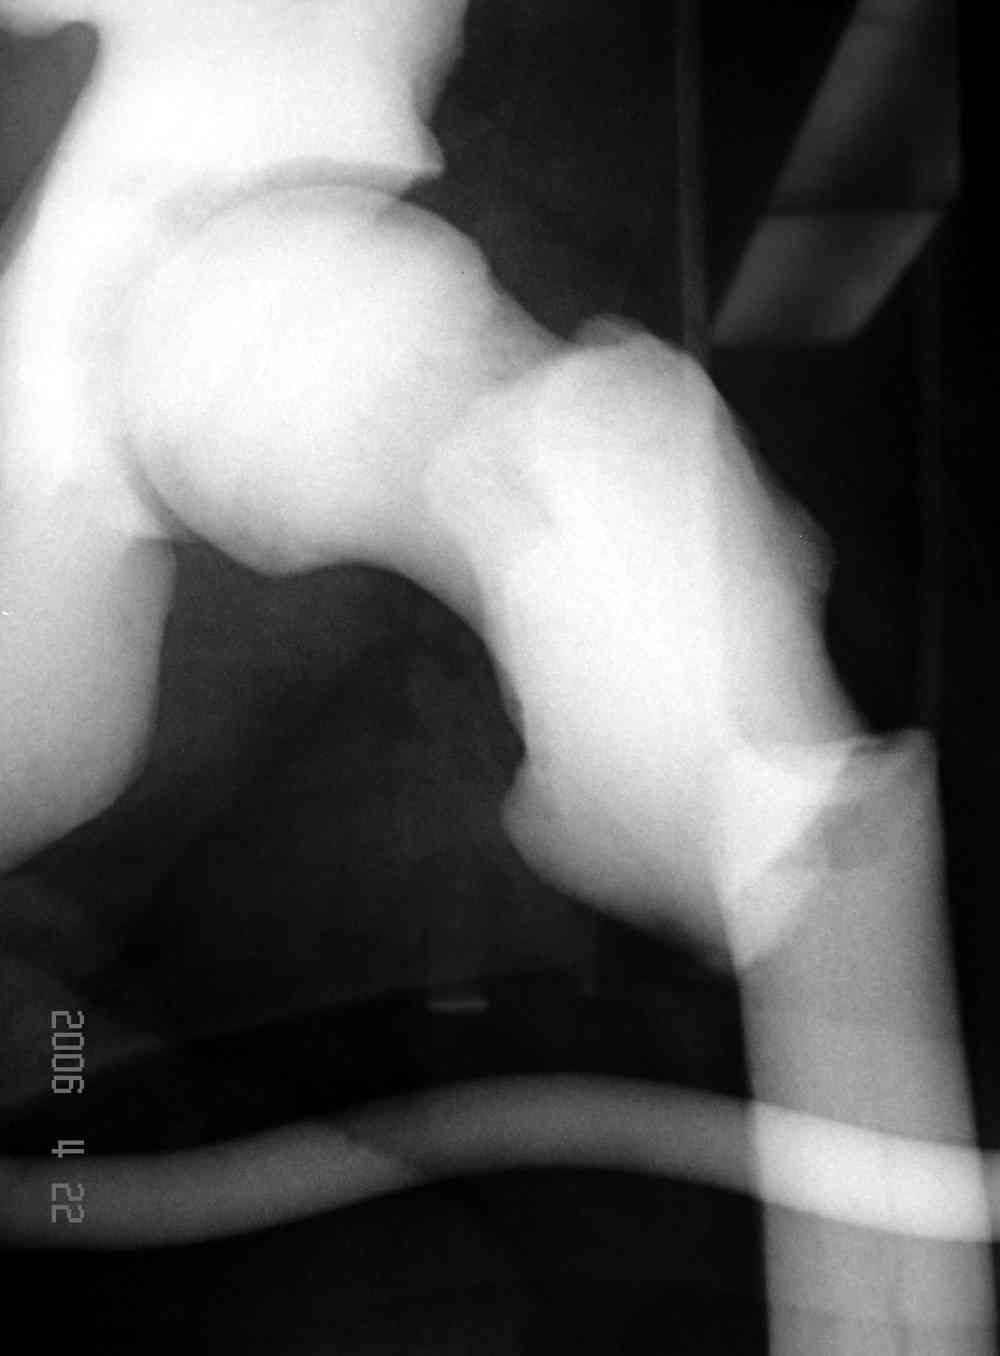

Здесь у меня дополнительные снимки с большим разрешением и в разных режимах, а то те дигитал снимки совсем очень блеклые, может, эти изображени изменят выбор тактики

Не вызывает ли подозрение, что отсутствует медуллярный канал, как просверлить канал?

Djoldas Kuldjanov > Не вызывает ли подозрение, что отсутствует медуллярный канал,

Канал, возможно, действительно запаян. Но разве большие проблемы его создать и рассверлить (если только это мраморная болезн?) Уверен, в вашей клинике есть для этого всё.